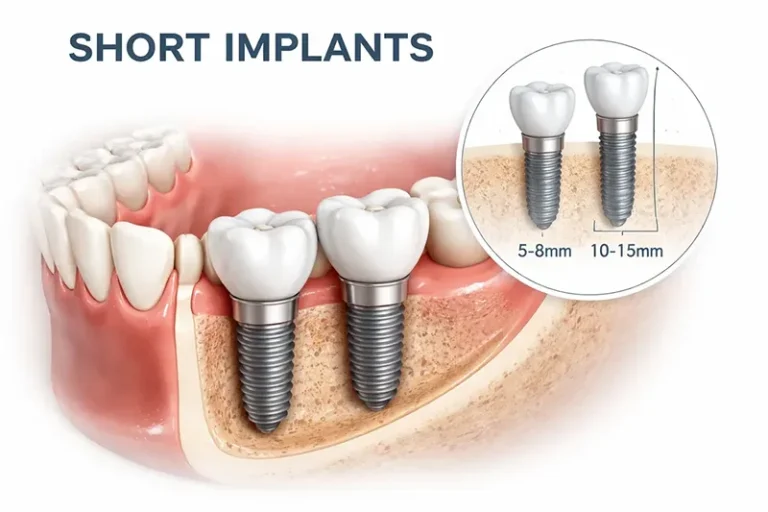

ایمپلنت پایه کوتاه

ایمپلنت پایه کوتاه یا شورت ایمپلنت Short Dental Implant یکی از روش های نوین در دندانپزشکی است

ایمپلنت پایه کوتاه یا شورت ایمپلنت Short Dental Implant یکی از روش های نوین در دندانپزشکی است